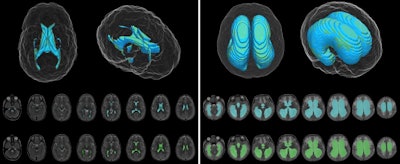

In the report, Stanford University neurosurgeon Dr. Jennifer Quon and colleagues explained how the deep-learning model was developed for the purpose of assessing changes in ventricular volume, as these signal how well treatment with a shunt works for reducing hydrocephalus. The researchers developed and validated the deep-learning model using T2-weighted MR images from 200 pediatric hydrocephalus cases and 200 controls. They also assessed the method on nine pediatric cases that were prospectively gathered.

In a comparison of deep-learning results with manual measures for ventricular volume assessments, segmentation accuracy was similar overall and better for patients with hydrocephalus, the team reported.